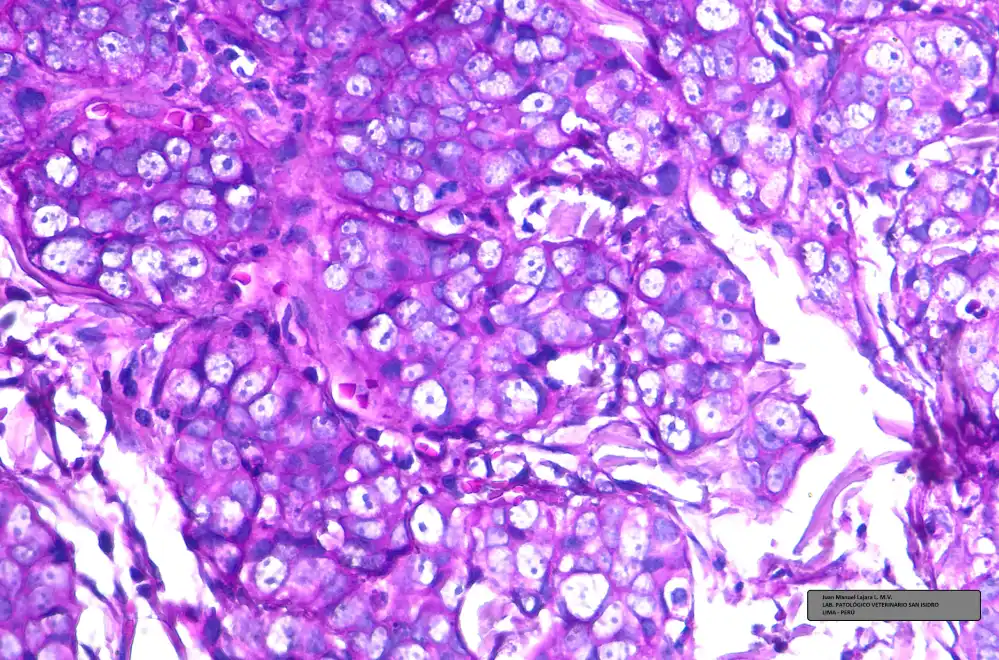

Las muestras para estudio histopatológico fueron coloreadas inicialmente con H-E (Hematoxilina – Eosina) y observadas al microscopio en múltiples aumentos. El resultado histopatológico produjo una inversión en los diferenciales previamente obtenidos por citología con los siguientes resultados:

- 1. ADENOCARCINOMA MAMARIO SÓLIDO Grado III (Alto Grado)

- 2. CARCINOMA DE CÉLULAS ESCAMOSAS (débil)

- 3. MASTOCITOMA (Muy débil)